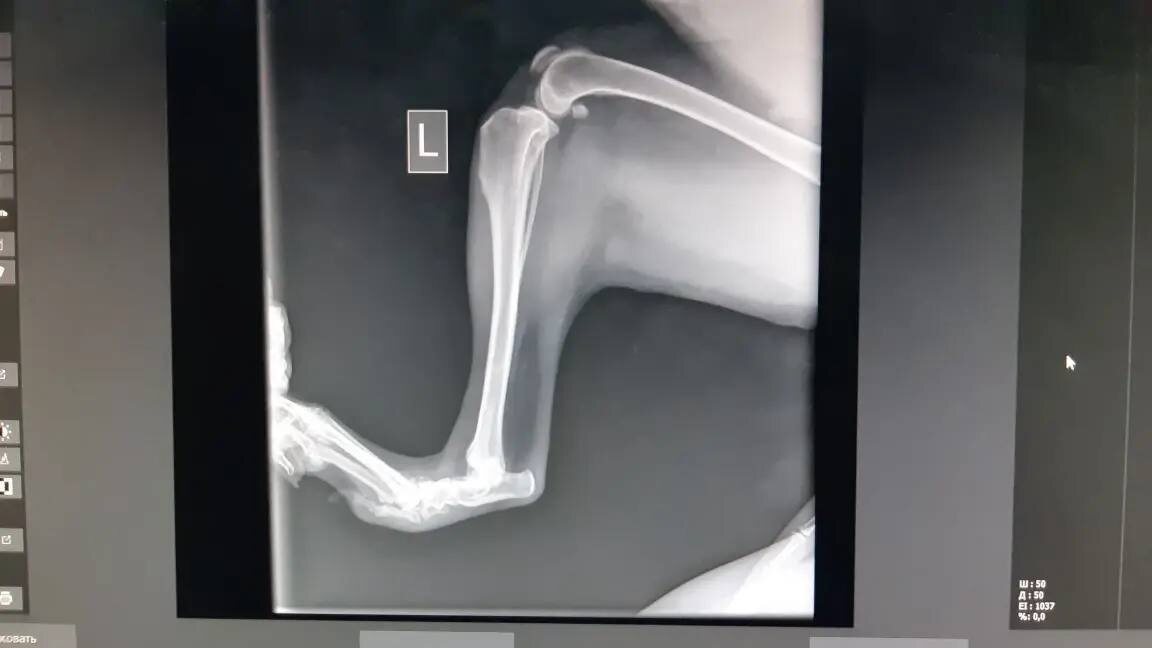

ЛюсИ.

У нашей красавицы застарелый вывих костей плюсны правой стопы. Нужен артродез.

Стоимость операции, примерно, 31’000 руб